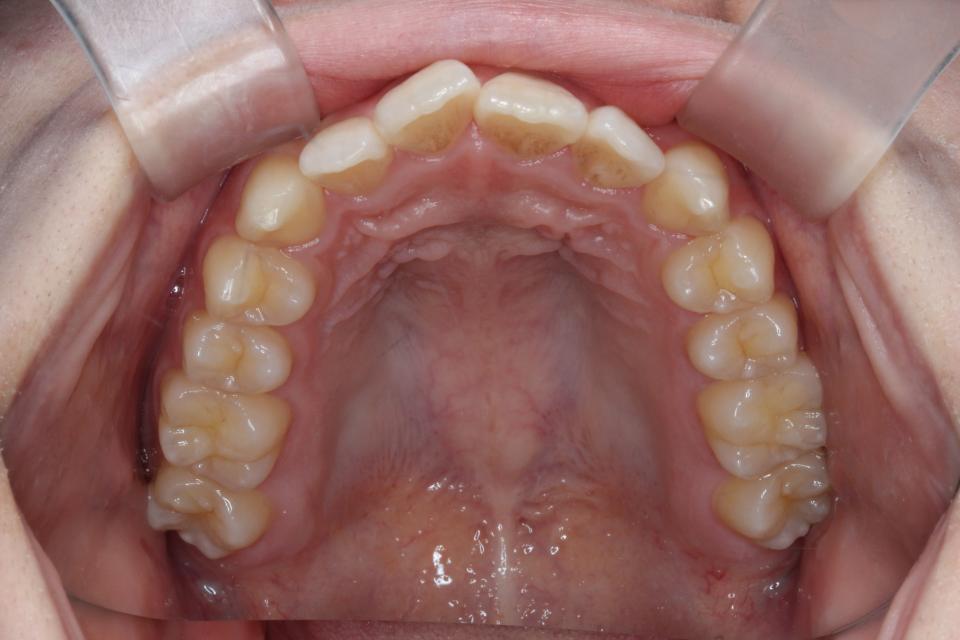

矯正治療前

20代女性の患者さんです。

上下の真ん中がズレているを気にして来院されました。

上下の歯にワイヤー(マルチブラケット装置)をつけて治療しました。

きれいに並びきるために歯のやすりがけ(IPR)も行っています。